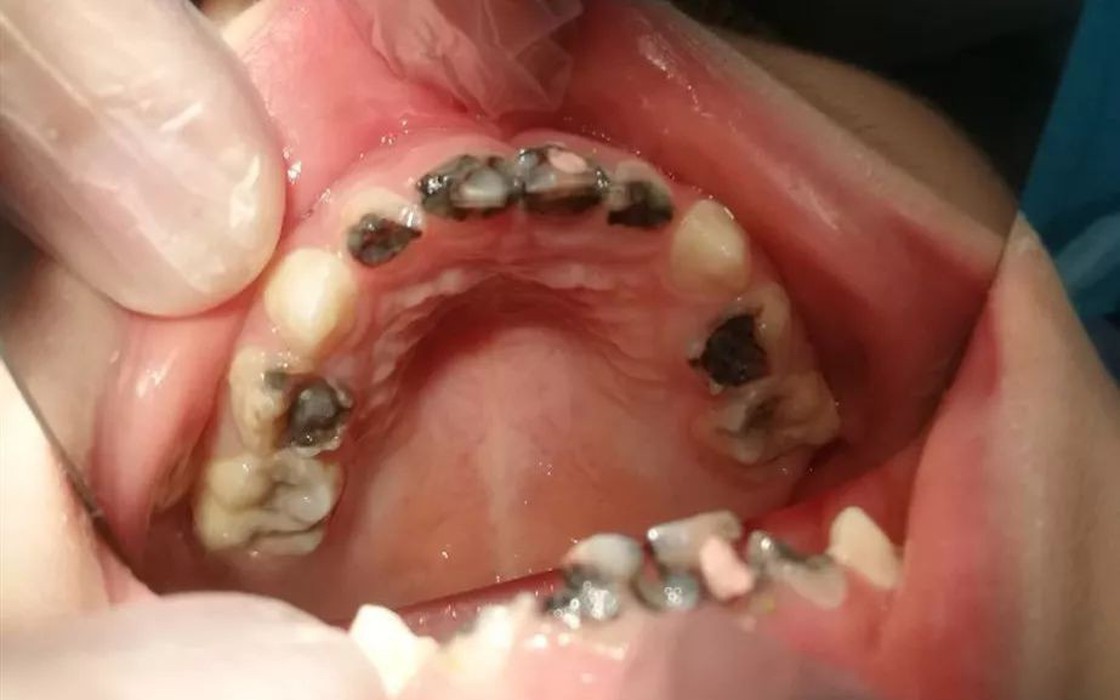

Bé 5 tuổi đã có 14 chiếc răng sâu

Mới đây, cô Trần sống tại Hải Khẩu, Trung Quốc đã dẫn con gái 5 tuổi tên là Tiểu Y đến bệnh viện khám. Khi đứa trẻ há miệng, bác sĩ vô cùng kinh ngạc khi thấy trong số 20 chiếc răng sữa thì có 14 chiếc răng đã bị sâu. Nhiều chiếc răng chỉ còn sót lại chân răng và cần phải tiến hành điều trị gấp.

Trong số 20 chiếc răng sữa thì có 14 chiếc răng đã bị sâu.